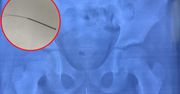

Co połknął dwulatek? Lekarka zaapelowała do rodziców